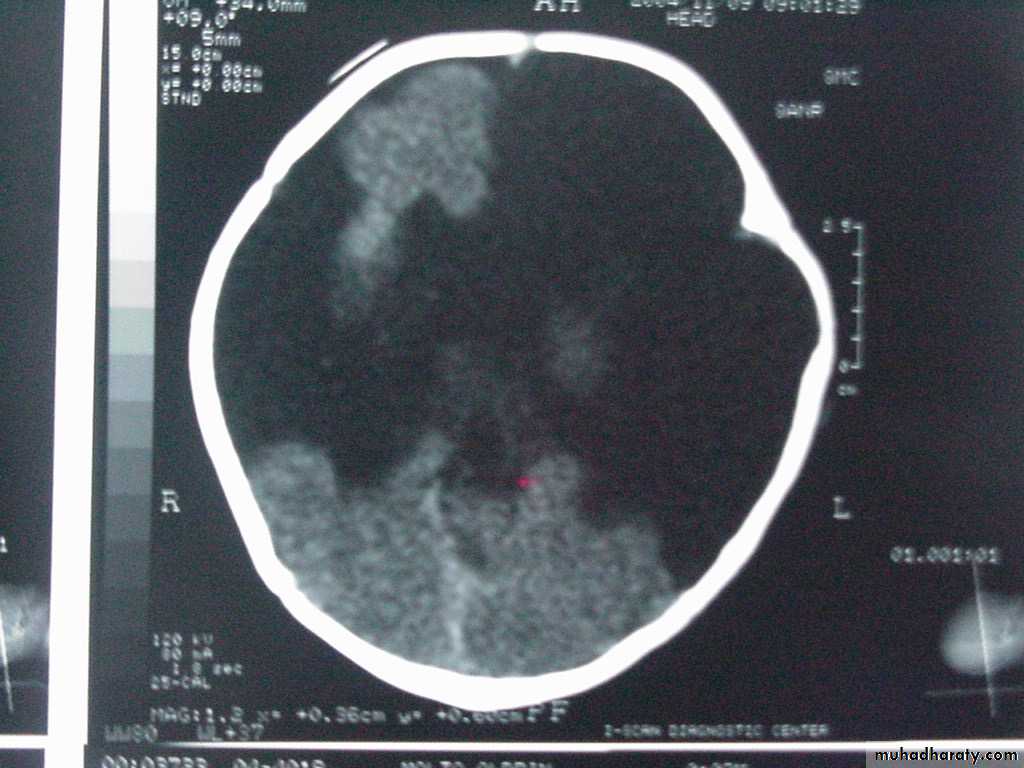

Porencephaly

Cysts or cavities within the brain that may or may not communicate with the ventricular system, resulting from vascular or infectious results during late fetal or early infantile lifeUsually present with hemiparesis and focal seizures during the 1st year of life

Agenesis of the Corpus CallosumResults from an insult to the commissural plate during embryogenesis

When it appears as an isolated phenomenon, the patient may be normal; but those with associated migration defects may present with Mental Retardation, microcephaly, hemiparesis, diplegia and seizures

CT/MRI: widely separated frontal horns with an abnormally high position of the 3rd ventricle